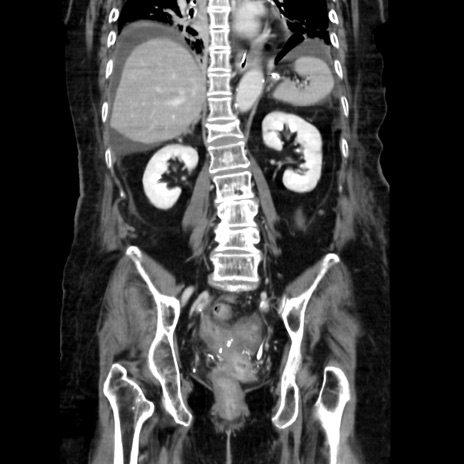

症例40(冠状断像)

【症例】90歳代女性

【主訴】腹痛・嘔吐

【現病歴】 食欲低下、嘔吐があり昨日他院受診。肺炎と診断され入院となる。入院後より腹部全体に圧痛あり。胃管留置され経過みていたが、症状持続するため、

当院転院となる。

【既往歴】胸椎圧迫骨折、胆石症

【身体所見】腹部:中央に激痛あり、圧痛あり、反跳痛不明

【データ】WBC 17100、CRP 18.82

冠状断像